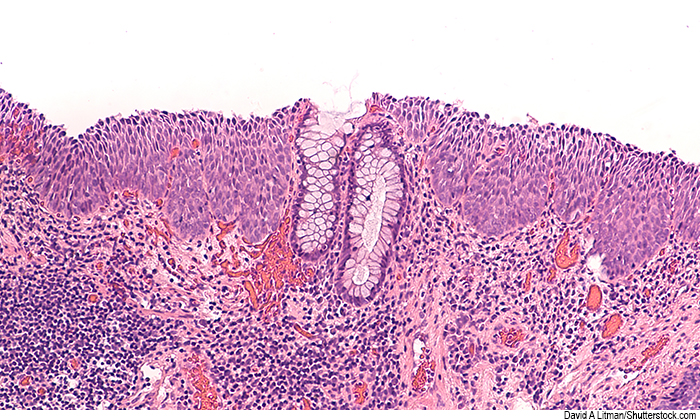

anal cancer cells

Like cervical cancer, anal cancer is caused by human papillomavirus (HPV), leading to precancerous high-grade squamous intraepithelial lesions that can progress to cancer.